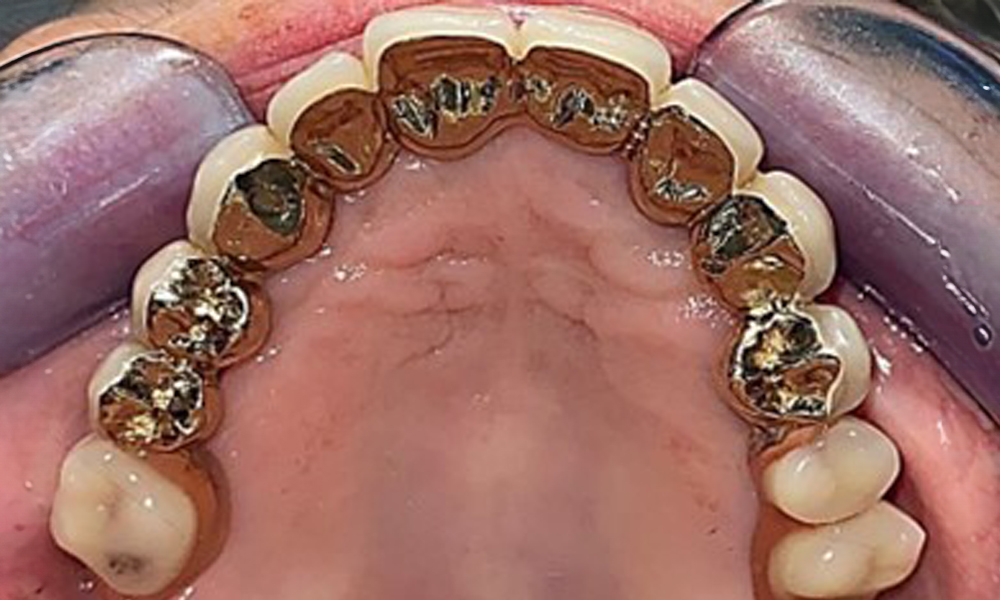

Оклузален изглед: Горна челюст със зъб и телескопични протези, поддържани от импланти

Фиг. 2: Оклузален изглед: Горна челюст със зъб и телескопични протези, поддържани от импланти

Денталните открития са следните: Комбинирани снемаеми протези на импланти и телескопични протези, поддържани от зъби, на импланти 15, 13, 21, 23, 24, 25 и зъб 11 (фиг. 1, фиг. 2, фиг. 3). Пациентът е снабден с фиксирана долночелюстна протеза. Над зъби 37-34 и 45-47 бяха налични адекватни мостове (фиг. 4), краищата на коронките бяха интактни и нямаше активен кариес. Върху зъб 43 имаше композитна пломба с маргинална празнина. Имаше рецесия на долната гингива, която разкриваше от 1 до 3 mm от кореновата повърхност. Това се отнася и за 11.